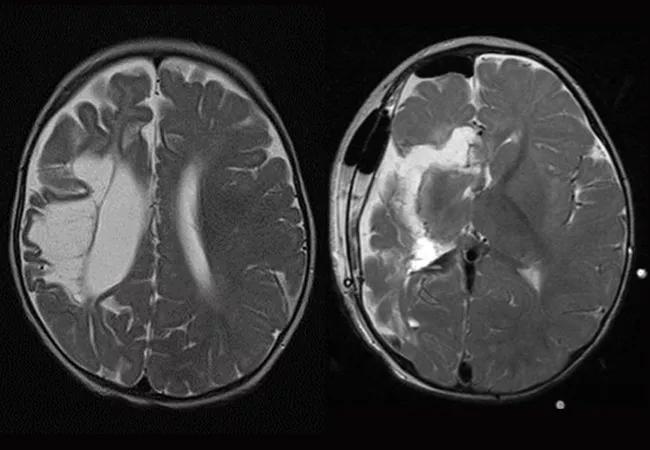

Recurrent seizures occur in approximately 50 percent of people who undergo surgery for temporal lobe epilepsy and in 60 to 70 percent of those who have surgery for extra-temporal lobe epilepsy.

The study will also assess timing of seizure recurrence. Dr. Jehi hypothesizes that “early” postoperative seizure recurrence is due to inaccurate localization of the lesion or incomplete resection, whereas “late” recurrence is due to genetic mechanisms that drive maturation of new seizure foci. Because surgery itself, like traumatic brain injury, has the potential to cause post-interventional or post-traumatic epilepsy, Dr. Jehi’s hypothesis has significant implications for predicting postoperative and post-trauma outcomes on the basis of a patient’s genetic makeup.